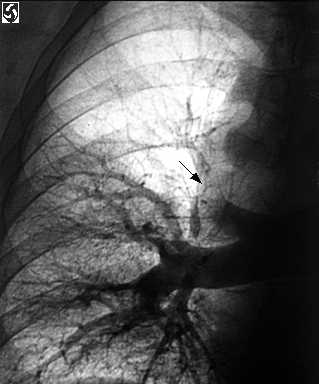

Selectivo derecho pulmonar angiogram

Pulmonar angiography da a conocer una oclusi�n y terminaci�n brusca ( flecha) de la sucursal subir de la arteria pulmonar derecho, el truncus anterior. El relleno de de fallas ( la flecha) est�n presente dentro de las arterias que abastecen los basal segmentos del l�bulo m�s inferior derecho.

La ingle derecho de paciente estuvo dispuesto y tapiz� usando t�cnica est�ril. El Seldinger de t�cnica se us� a percutaneously punzada la derecho com�n femoral la vena con un 18 indicador separa - tapiada de aguja. Un 7 Franc�s pigtail catheter se puso en el inferior vena cava sobre un J-guide el est�ndard cable. El cable se quit�. Un yodo alto (350 mg/ml) nonionic contrasta de medio se infundi� en el catheter y un inferior venacavagram mostrado que el cava estuvo sin thrombus. El catheter se dirigi� mediante el atrio derecho, ventr�culo derecho, extensi�n pulmonar de efusi�n, y arteria pulmonar principal. Las grabaciones de presi�n dadas a conocer una levemente elev� la presi�n principal de arteria pulmonar (37/15 mmHg, significa de 17 mmHg). La presi�n normal de arteria pulmonar era 20-25/8-12 con una significada presi�n de 15. Desde este paciente V/Q repasa mostr� pulm�n predominantemente derecho perfusion fallas, la substracci�n digital selectiva angiography del pulm�n derecho se desempe��. Los derecho pulmonar arteriogram los im�genes mostraron cesaci�n brusco del truncus anterior por occlusive thrombus. Hab�a tambi�n intraluminal fallas de relleno dentro de basilar arterias l�bulo a la derecha m�s inferior. Estos hallazgos proveyeron diagn�stico definitivo de PE.